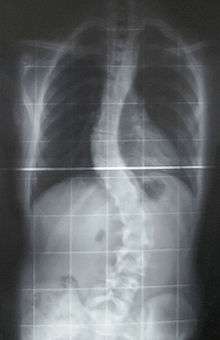

The prognosis of this sub-type of MD indicates that the affected individual may eventually have feeding difficulties. Surgery, at some point, might be an option for scoliosis.[7]

Scoliosis which is a sideways curve of the persons vertebrate, is determined by a variety of factors, including the degree (mild or severe), in which case if possible a brace might be used by the individual[9]